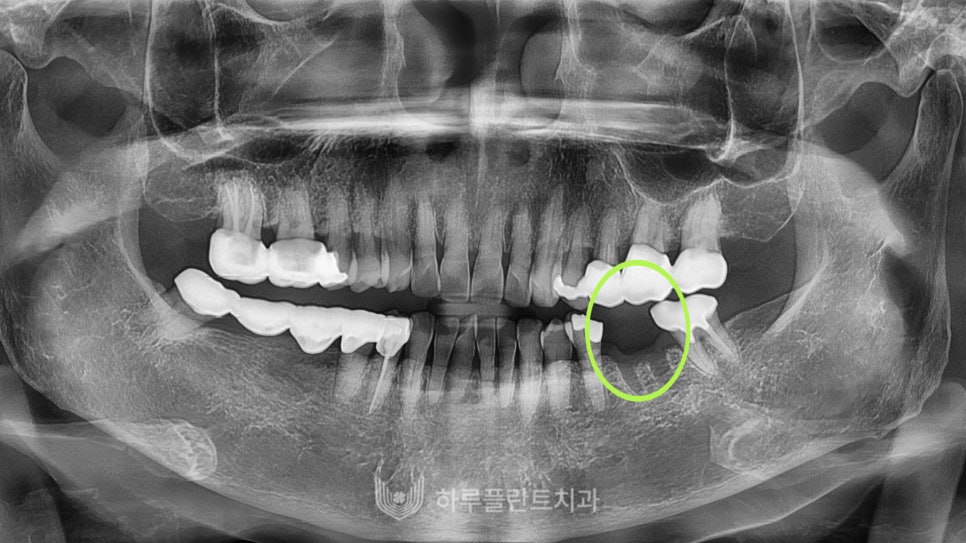

강남구 당일 임플란트 성공 케이스 2

23.05

두번째 환자분은 타 치과에서

한 달 전 밭치를 하고 당일 임플란트를 위해

저희 치과를 찾아오셨습니다.

발치 부위가 많이 아문 상태였어요~

환자분께서 임플란트 수술이 처음이라

처음에 많이 긴장한 모습을 보이셨는데요

변성만 대표원장님께서 긴장을 풀어드리고

편안하게 수술을 진행했습니다.

성공적으로 아주 잘 식립되었고

당일 보철물 장착까지 마무리하고 귀가하셨습니다.